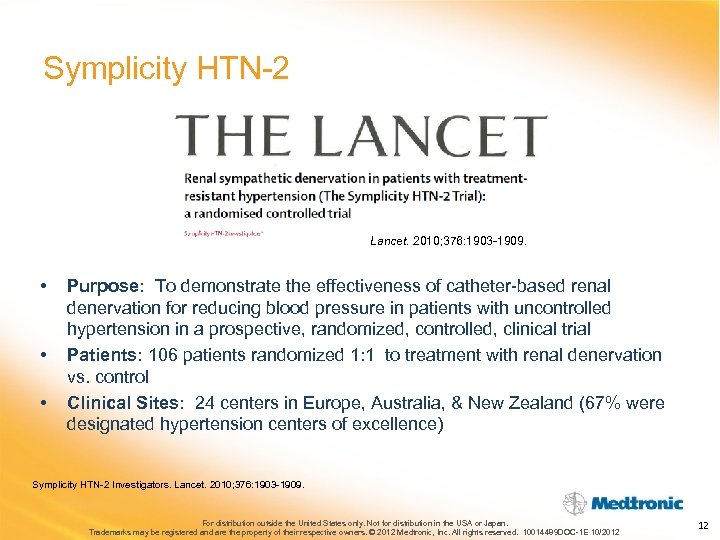

Symplicity HTN-2 Lancet. 2010; 376: 1903 -1909. • • • Purpose: To demonstrate the effectiveness of catheter-based renal denervation for reducing blood pressure in patients with uncontrolled hypertension in a prospective, randomized, controlled, clinical trial Patients: 106 patients randomized 1: 1 to treatment with renal denervation vs. control Clinical Sites: 24 centers in Europe, Australia, & New Zealand (67% were designated hypertension centers of excellence) Symplicity HTN-2 Investigators. Lancet. 2010; 376: 1903 -1909. For distribution outside the United States only. Not for distribution in the USA or Japan. Trademarks may be registered and are the property of their respective owners. © 2012 Medtronic, Inc. All rights reserved. 10014489 DOC-1 E 10/2012 12

Symplicity HTN-2 Lancet. 2010; 376: 1903 -1909. • • • Purpose: To demonstrate the effectiveness of catheter-based renal denervation for reducing blood pressure in patients with uncontrolled hypertension in a prospective, randomized, controlled, clinical trial Patients: 106 patients randomized 1: 1 to treatment with renal denervation vs. control Clinical Sites: 24 centers in Europe, Australia, & New Zealand (67% were designated hypertension centers of excellence) Symplicity HTN-2 Investigators. Lancet. 2010; 376: 1903 -1909. For distribution outside the United States only. Not for distribution in the USA or Japan. Trademarks may be registered and are the property of their respective owners. © 2012 Medtronic, Inc. All rights reserved. 10014489 DOC-1 E 10/2012 12